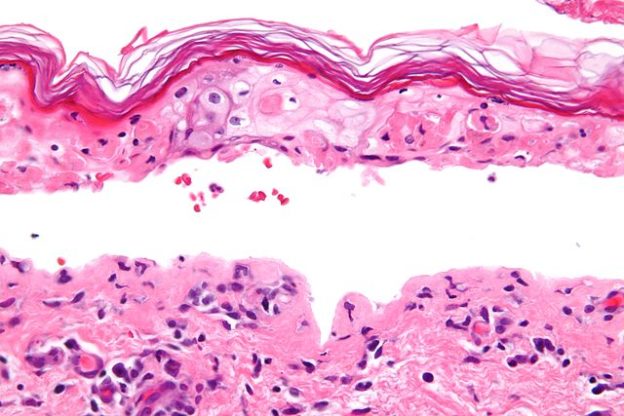

병리조직학적 소견에서 TEN과 SJS는 표피의 염증성 세포 침윤을 동반하고 표피 기저층 또는 표피 전층에 호산성 괴사가 나타납니다. 면역조직화학염색상 각질형성세포의 MHC클래스2항원(HLA-DR) 발현과 세포유착분자(ICAM-1) 발현, 표피랑겔한스세포의 현저한 감소 및 소실, 표피의 CD8+세포침윤, 진피에 CD4+세포침윤이 따릅니다. 이러한 소견은 세포독성 T세포에 의한 이식편대 숙주 조직반응과 비슷합니다. TEN은 각질형성세포와 Fas리간드(FASL) 발현이나 세포고사, 수포 내 TNF-알파가 증가하므로 각질형성세포의 세포고사 및 TNF-알파에 의한 조직손상이 유발됩니다.

병리 조직학적 검사에서는 다양한 정도의 표피괴사가 동반됩니다.진피와 표피의 경계부에서 공포와 융합에 의해 열을 형성하고 이후 표피하소포가 형성되면서 여러 정도의 염증세포(대부분 림프구)가 침윤하고 유두진피에 호산구의 침윤이 나타납니다.수포성 유선포창, 반흔성 유선포창, 포진성 피부염, 심상성 천포창, 종양관련성 천공창, 혈관염, 베체트병, sweet증후군, 포도상구균성 열상피부증후군, 포진성 치육구내염, 급성이식 편대숙주반응과 감별해야 합니다.